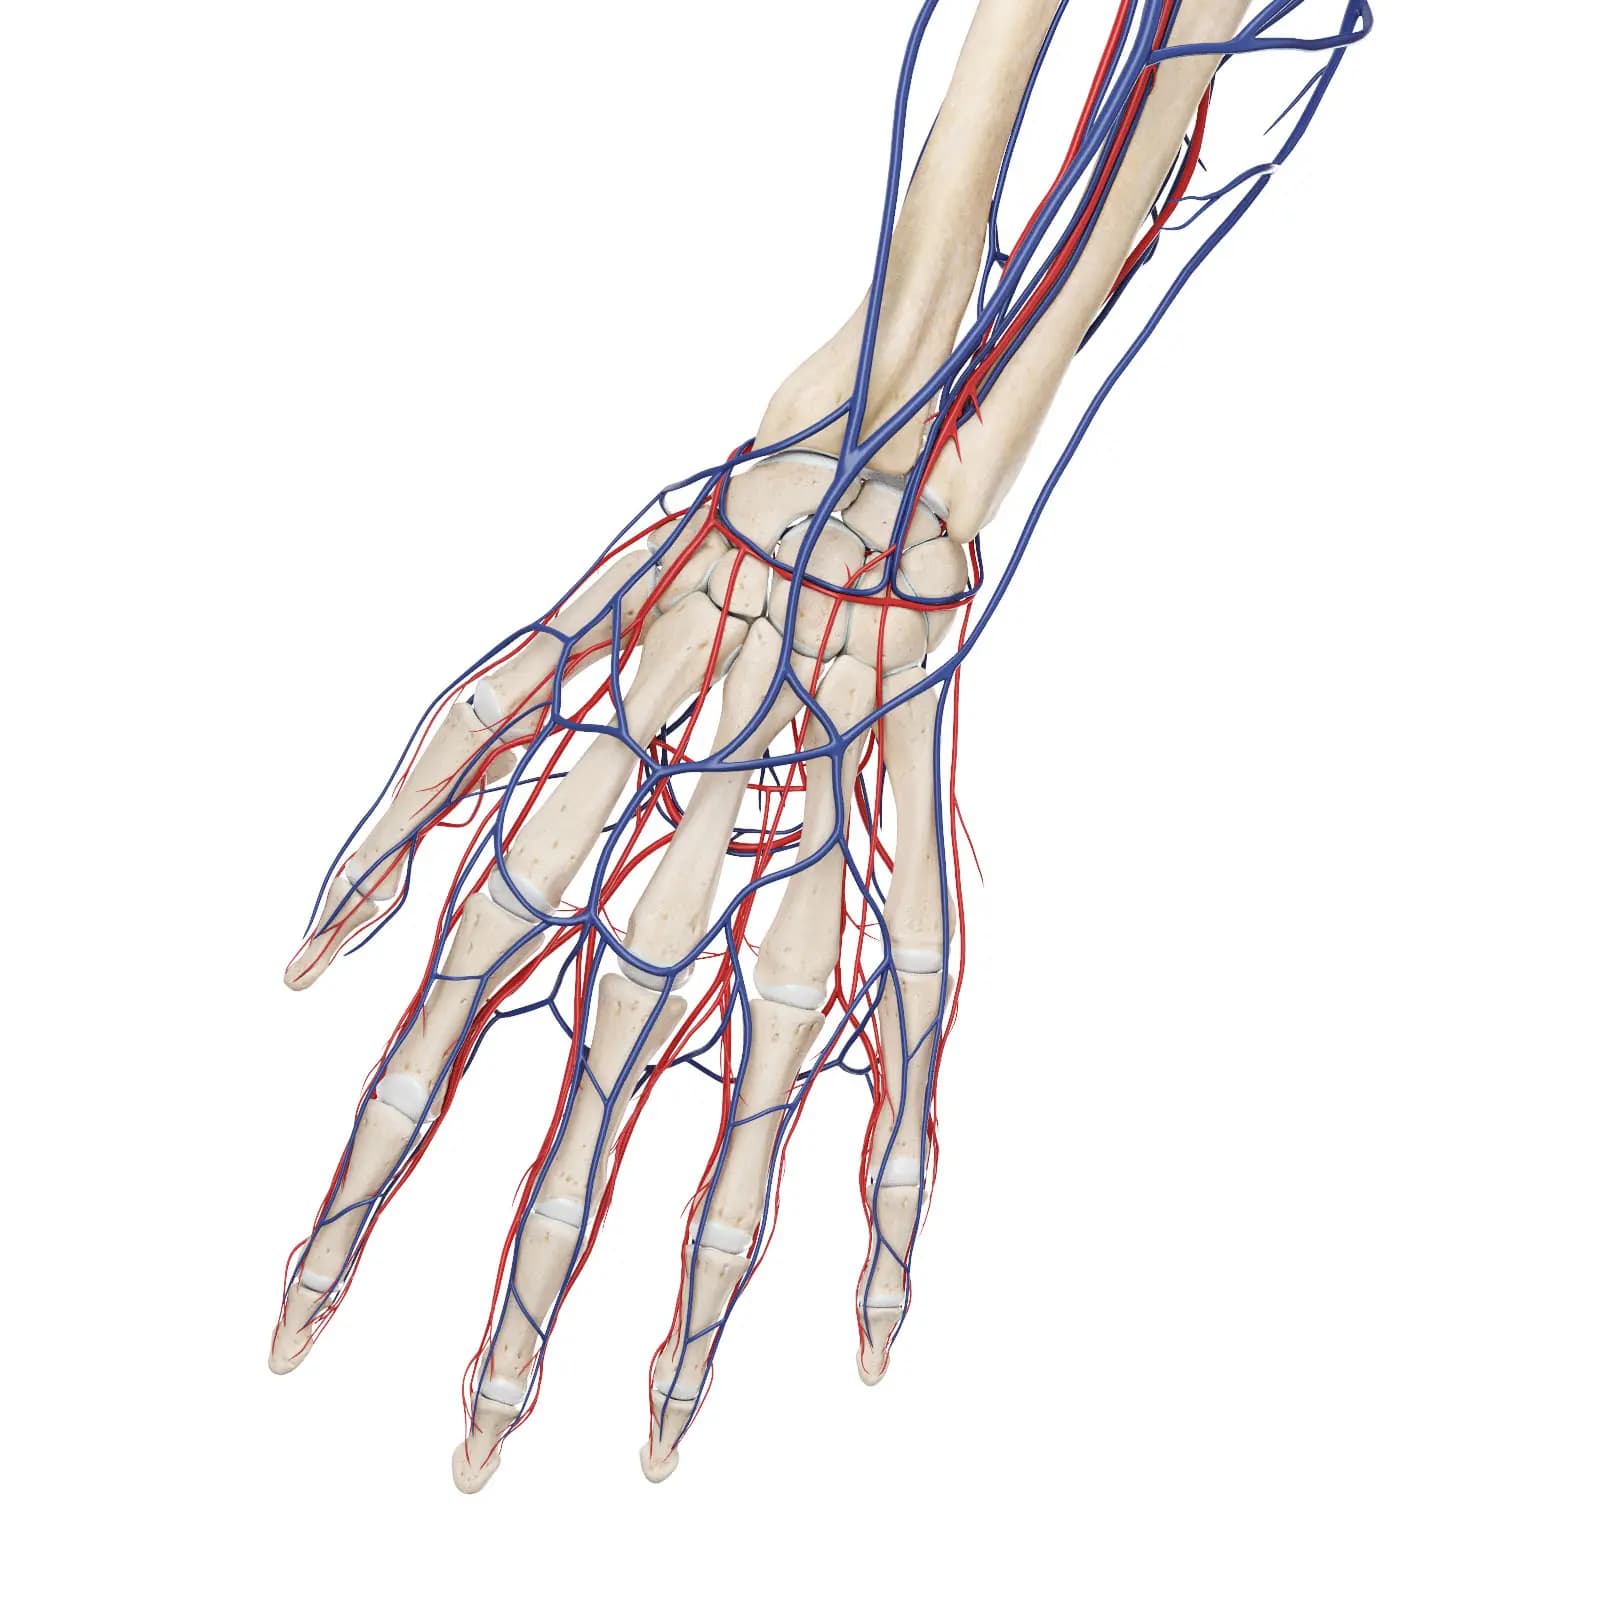

3d Rendered Medical Illustration Of The Vascular System Of The Hand